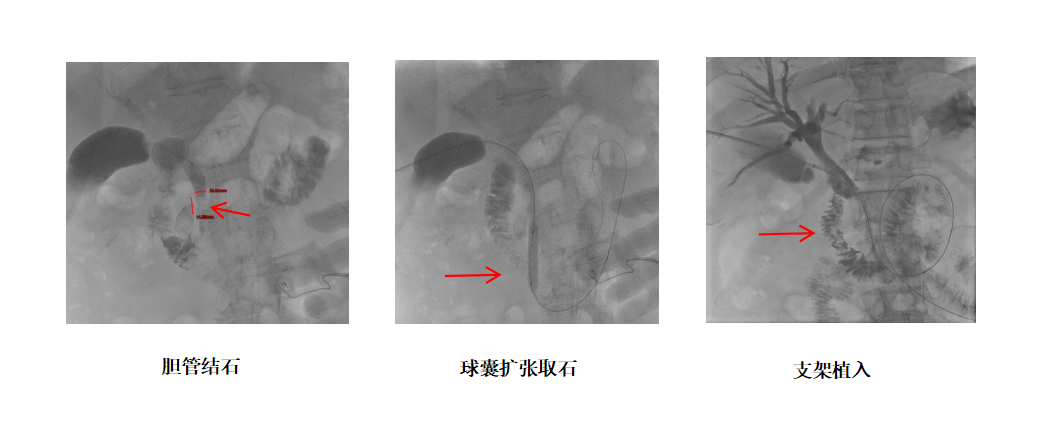

★针对结石患者:团队沿通道进入胆总管,利用球囊扩张十二指肠乳头括约肌,巧妙运用网篮或球囊将结石顺利推入十二指肠,实现了微创取石。该技术的另一大优势在于,它通过球囊扩张十二指肠乳头括约肌,是一种可恢复的、非破坏性的操作,完美避免了腹腔镜或内镜下括约肌切开术可能造成的永久性损伤。由于括约肌的生理功能得以保留,从长远看,术后因肠液反流导致的胆道感染并发症也得以有效避免。该方法避免了传统开腹手术的大创伤,也弥补了内镜逆行的不足。

★针对恶性梗阻患者:通过此路径成功引流淤积的胆汁,有效降低黄疸、改善肝功能,为后续治疗赢得了宝贵时间,并可进一步植入支架,实现长期引流。

通过建立的通道,使用球囊取石或胆管癌植入支架